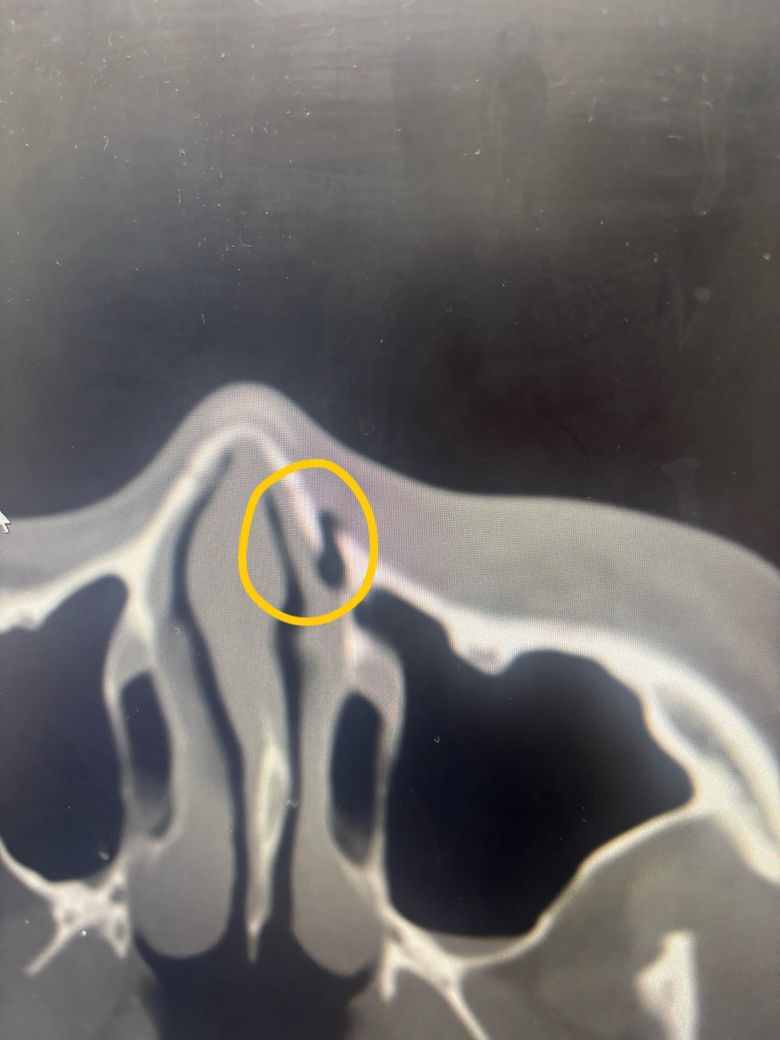

그리고 오늘 병원 갓다오니깐 코랑 입쪽 연결되는 부분의 뼈는 골절이 맞는데 심하지 않다고 수술은 안해도 된다고 하는데 수술을 안해도 자연스럽게 붙나요 뼈가 ?? 이빨도 제가 지금 맞아서 치과 치료도 받아야되는디 입도 못벌리는 상황이구요

사진 1 번째가 입과 코연결되는 부분이고